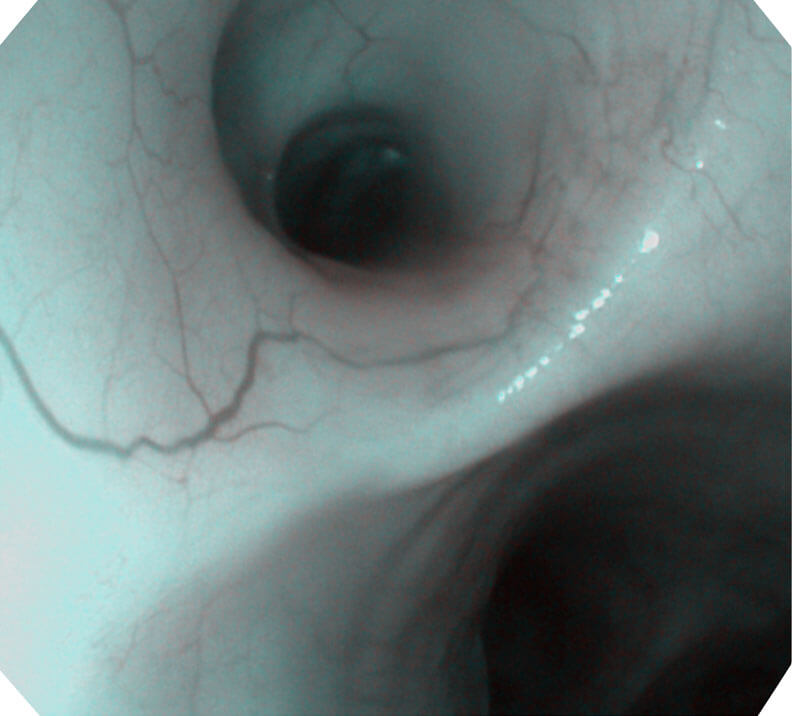

帮助医生更加清晰地观察气管表面病灶

120°视场角,满足更大视野范围的观察。配合 VIST 染色,助力呼吸系统疾病的诊断。

(Versatile Intelligent Staining Technology, VIST)

光电复合染色成像技术(VIST)是一种光学滤波和数字滤波相结合的染色成像技术,摒弃了滤光转轮而直接采用光谱组合的方案,加入了血红蛋白吸收高峰与次高峰的蓝紫光和绿光光谱,更有利于黏膜血管吸收,突显浅表层血管和中层血管的对比度,因而具备更高的图像对比度,有助于观察微细结构变化及病灶边界的观察。